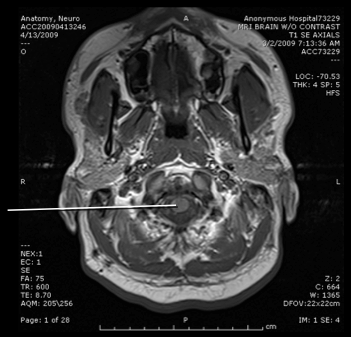

spinal cord

medulla

cerebellum

4th ventricle